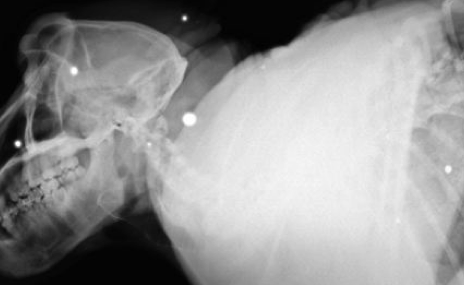

Nyt verkossa on julkaistu röngtenkuvia kuolleesta Fred-nimisestä paviaanista, joka aiheutti kauhua Etelä-Afrikan Kapkaupungin asukkaiden keskuudessa. Vandaalin maineen saanut paviaani ammuttiin kuoliaaksi sen väkivaltaisen ja uhkaavan käytöksen takia. Eläinlääkärien julkaisemat röngtenkuvat paljastavat, että Fred-paviaaniin on ammuttu yli 50 luotia. Kuvissa nähdään, kuinka paviaanin vartalossa näkyy valkoisia luodinjälkiä.